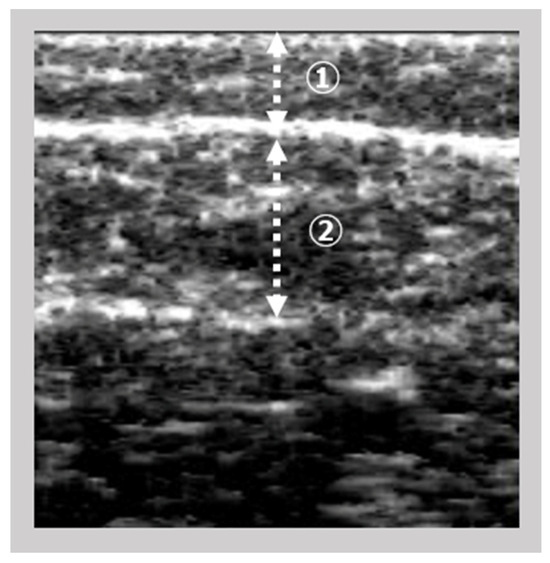

2.2.1. Ultrasonography